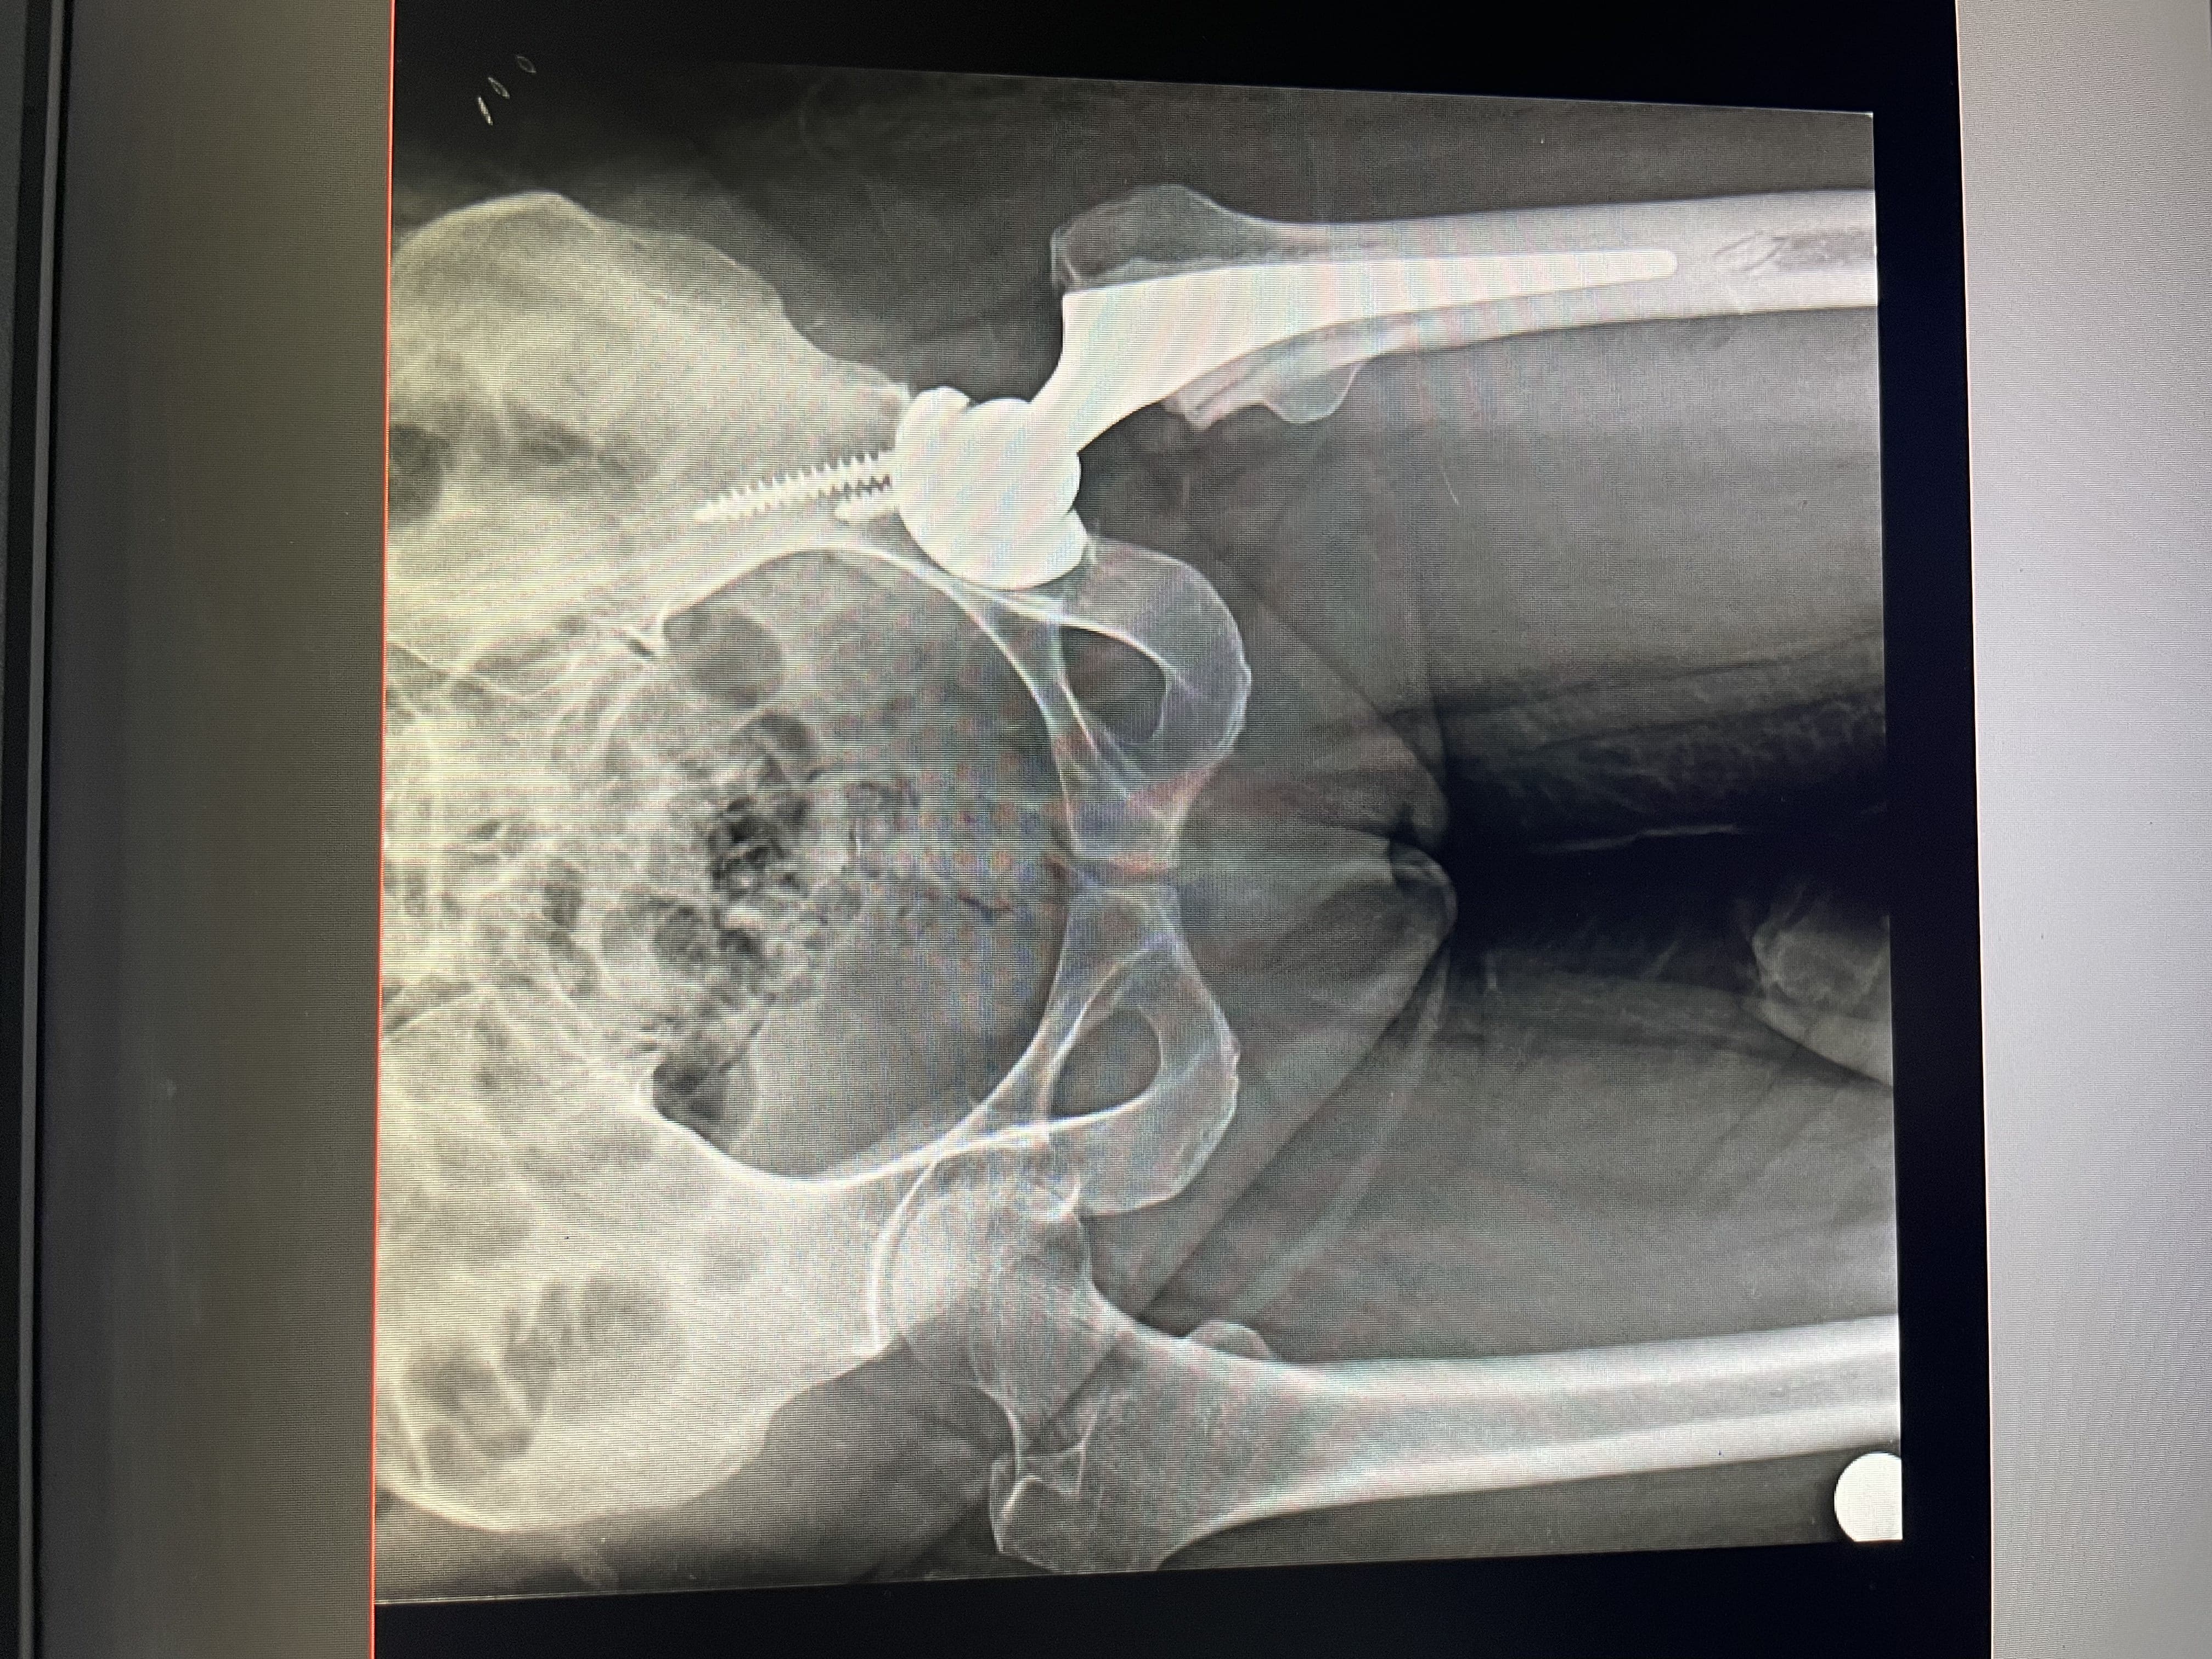

Images of Hip Replacement:

X-Ray of Knee Replacement 1

Hemiarthroplasty/ Partial Hip Replacement: The ball is replaced with a highly polished metal ball on a metal stem. The hip socket is not replaced. This is performed in older patients with hip fractures.